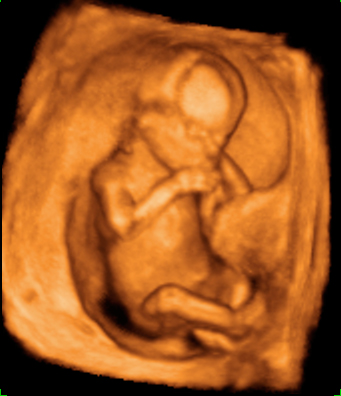

Ecografía 4D de la semana 12: Feto moviéndose de perfil

La ecografía 4D muestra al bebé moviéndose a sus anchas en el útero materno. Este plano de perfil muestra brazos, piernas y cordón umbilical en movimiento constante, lo que es es signo de vitalidad fetal. Las estructuras básicas de un feto de 12 semanas de gestación se parecen mucho a las de un bebé recién nacido; es ya todo un niño, aunque le falten unos seis meses aproximadamente para ver la luz.

Ecografía 4D: feto de 12 semanas moviéndose de perfil